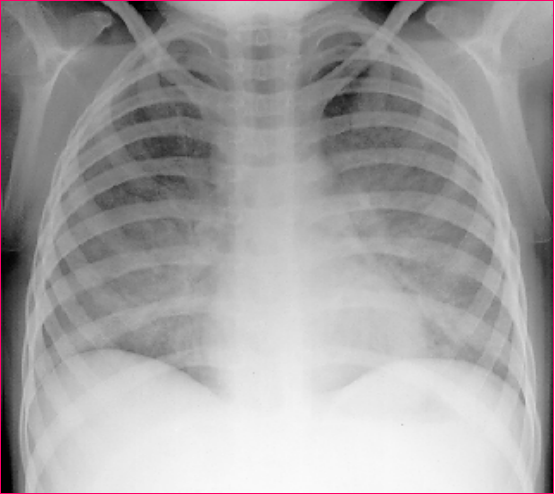

卡氏肺囊虫所致间质性肺炎

4 岁半女孩患卡氏肺囊

虫所致间质性肺炎(心脏

手术后)胸部 X 线检查:

典型均一性毛玻璃状浑

浊,下野特别明显